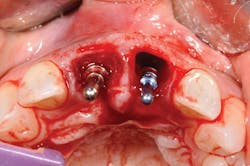

Figure 5: Implant and bone graft completed on No. 8, and implant placed on No. 9.

Extractions are a horrifying concept, yet in actuality there is pressure but no pain. Tooth No. 8, as predicted, shattered with the first touch (see Figure 3). The sound was terrible, a super loud snap. It took a moment for me to regroup, take a breath, and literally grieve the loss of my front tooth. It sounds ridiculous, but for me this was my true moment of loss, and then beginning. The prosthodontist decided that we would prepare each tooth individually, from start to finish. One tooth out, lots of drilling to remove the root, then synthetic bone-graft material mixed with my own bone (see Figure 4). As it happens, I was offered bovine bone, treated cow bone. As a nonmeat eater, there was not a chance I could handle that in addition to losing my two front teeth! Choosing synthetic was a personal option for me. Let your patients know there are cow, pig, cadaver, and synthetic materials available; it is a personal choice (see Figure 5).